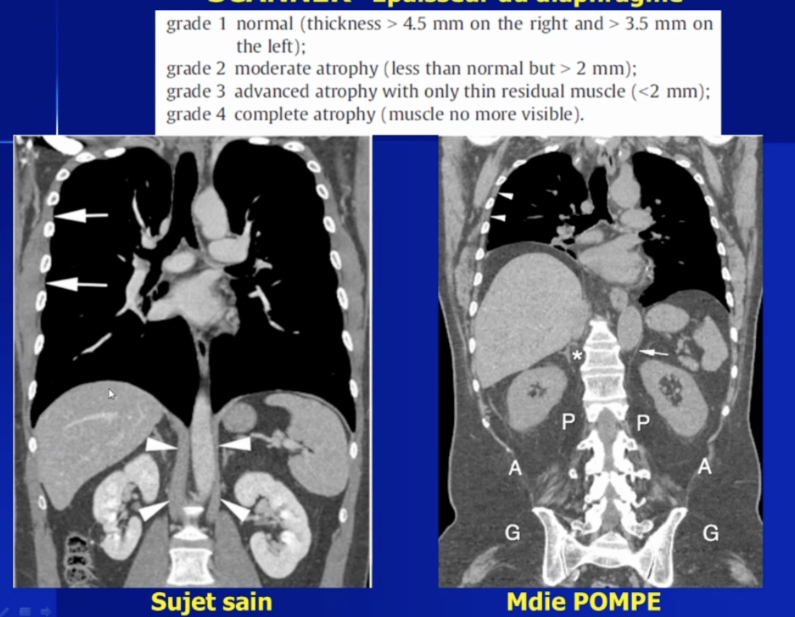

Epaisseur du diaphragme en CT

Analyse Morphologique en T1FS et T2

- Piliers du diaphragme

- Trophicité / Epaisseur du diaphragme